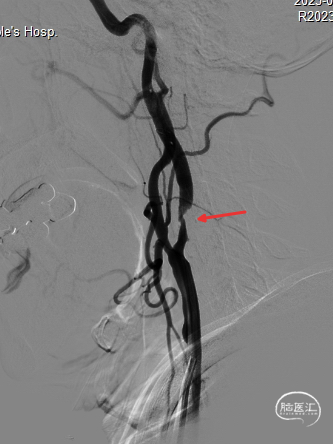

撤出保护伞观察10分钟复查造影,无弹性回缩,狭窄明显好转,血流明显改善(箭头处),结束手术。